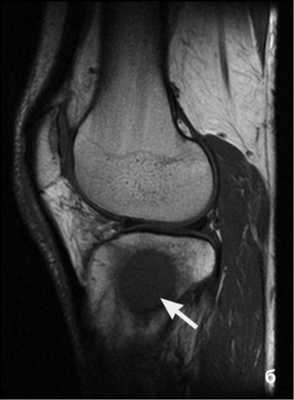

МРТ: симфизит, стрелка указывает на утолщение капсулы, неровность контуров

В основе исследования лежит принцип магнитного резонанса - фиксации перемещения ионов водорода под влиянием создаваемого аппаратом поля и электрических импульсов с последующей визуализацией данных с помощью компьютерной программы. Рентгеновского излучения, способного нанести вред человеческому организму, нет. Диагностическая процедура подходит для обследования беременных со второго триместра гестации и новорожденных в возрасте от 1 месяца. Для получения более контрастных снимков используют внутривенное введение препарата с парамагнетическими свойствами на основе хелатов редкоземельного металла гадолиния.